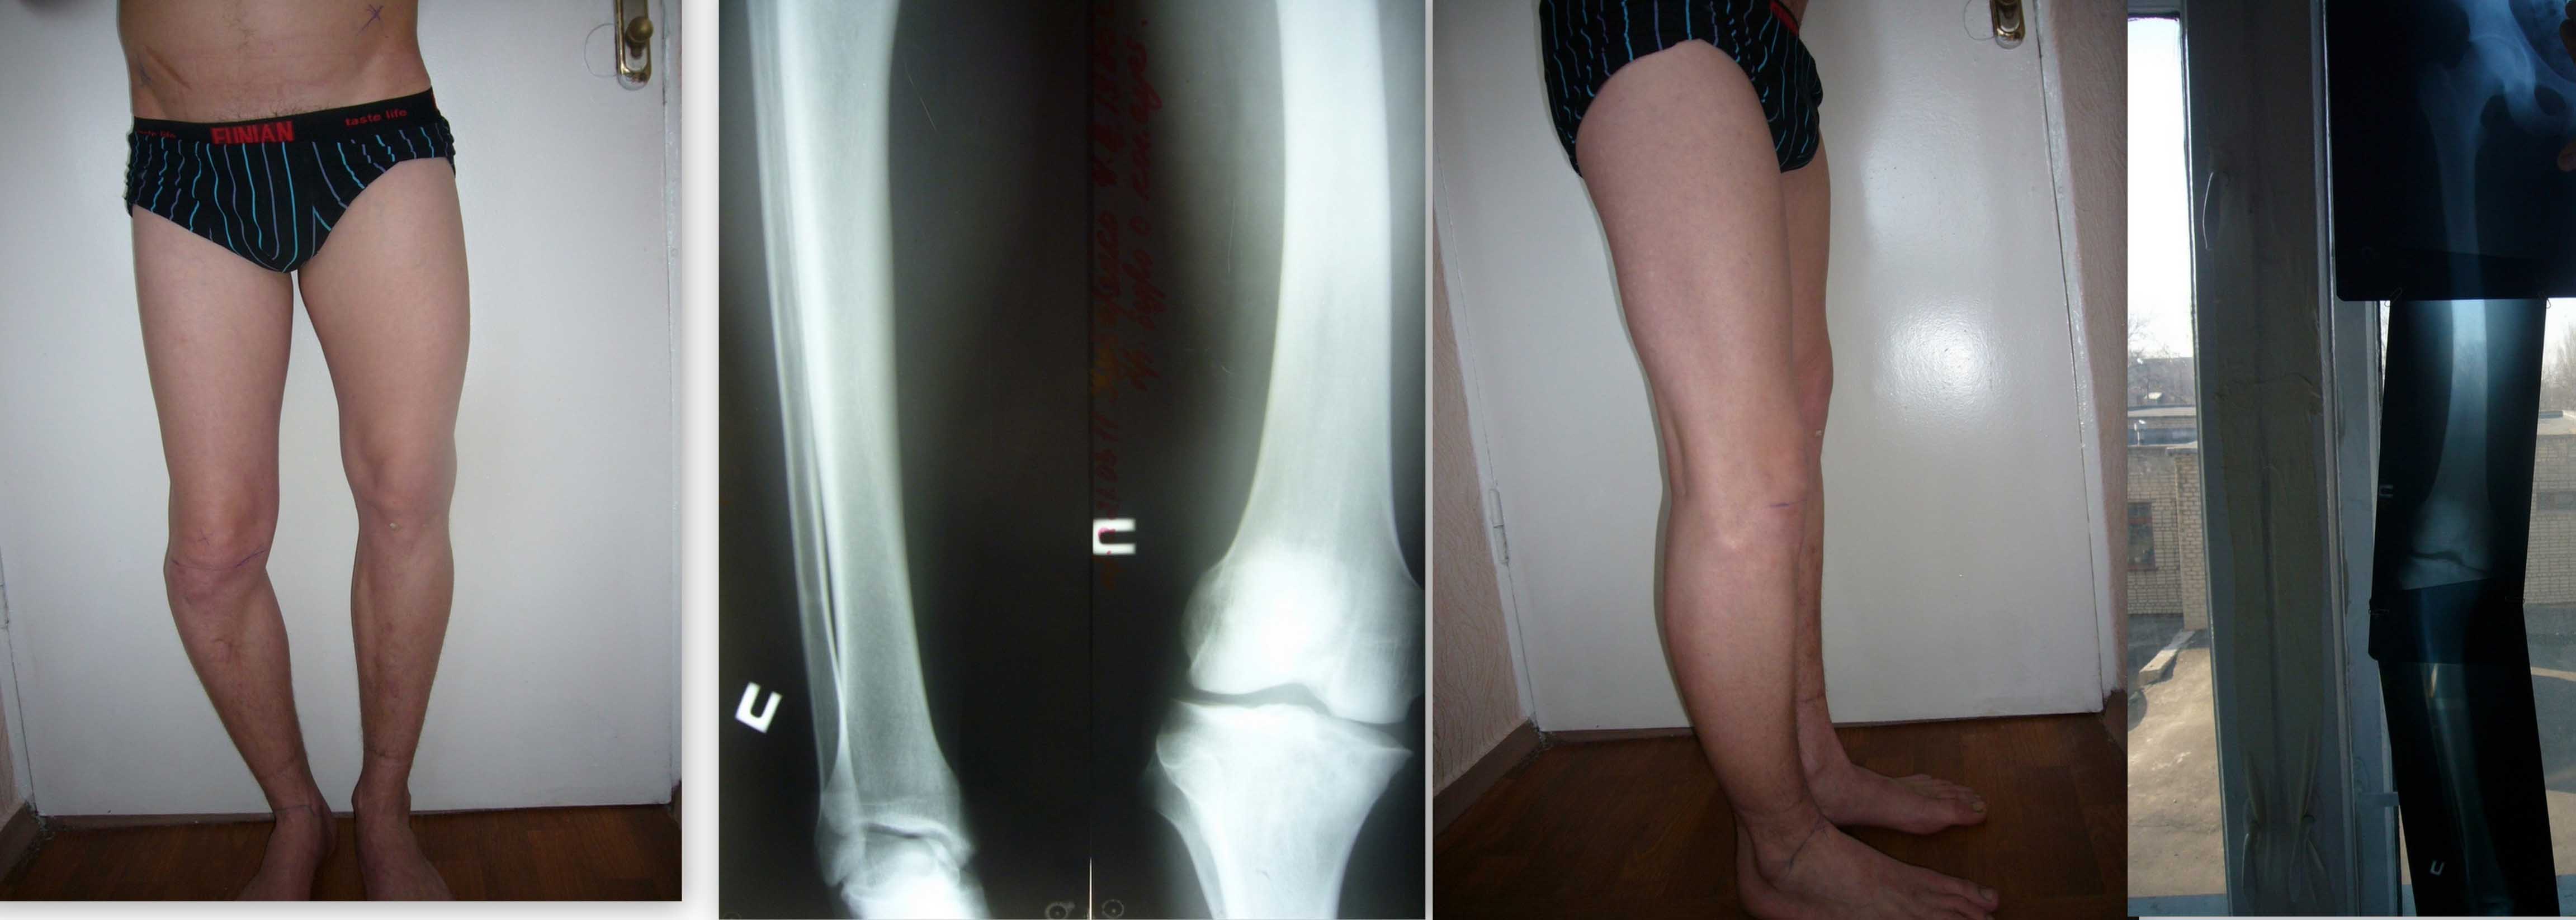

Здравствуйте уважаемые коллеги! К нам обратился интересный больной. Парень 25 лет.

В детстве перенёс гематогенный остеомиелит правой голени и бедра. До 5 лет частые флегмоны бедер и голени.

Соматически сохранен, укорочение до7 см. правой нижней конечности.

Планируем аппаратное устранение с остеотомией голени и бедра.

Уровни остеотомии?

Одномоментное или этапное устранение деформации?